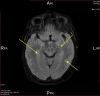

Acute disseminated encephalomyelitis (ADEM) is an immune-mediated phenomenon characterized by demyelination of the central nervous system that displays numerous manifestations. It predominantly presents in children with a mean age range of five to eight years. ADEM remains a diagnosis of exclusion based on clinical and radiographic progression. Thus, it poses a diagnostic challenge. ADEM has been shown to be very responsive to steroids and exchange therapy. Here, we present an unusual case of ADEM in a 50-year-old female patient who, despite receiving an entire course of IV methylprednisolone and other conventional treatment methods, did not respond to the treatment.